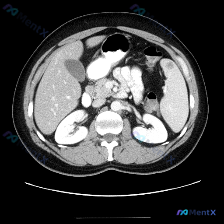

整理了一份很有意思的影像分析素材——预设是「脾脏病变」,但看完图像和完整序列逻辑后,发现值得拿出来聊聊整个分析思路。 --- 先看影像基础信息 这是一张腹部增强CT横断面图像(软组织窗): - 对比剂强化明显(腹主动脉、下腔静脉高密度显影) - 图像质量良好,无明显伪影,解剖结构显示清晰 系统阅片的...

看到一个资料,问题直接指向「脾脏病变」,附上了一张腹部增强CT的横断面图像。整理一下读片和分析思路,这个病例的核心其实不是「找病变」,而是「怎么面对阴性结果」。 病例影像基础信息 - 检查手段:腹部CT横断面,软组织窗 - 增强状态:根据血管及实质强化,考虑为静脉期/平衡期 - 扫描层面:上腹部,包...

今天看到一份影像资料,原始标注是「Splenic lesion(脾脏病变)」,但仔细读片后觉得这个预设结论值得商榷,整理一下思路和大家讨论。 先看完整影像信息 - 影像类型:腹部横断面(轴位)T2加权图像 - 图像质量:对比度良好,解剖结构清晰,无明显伪影 - 肝脏评估:形态大小正常,肝叶比例协调,...